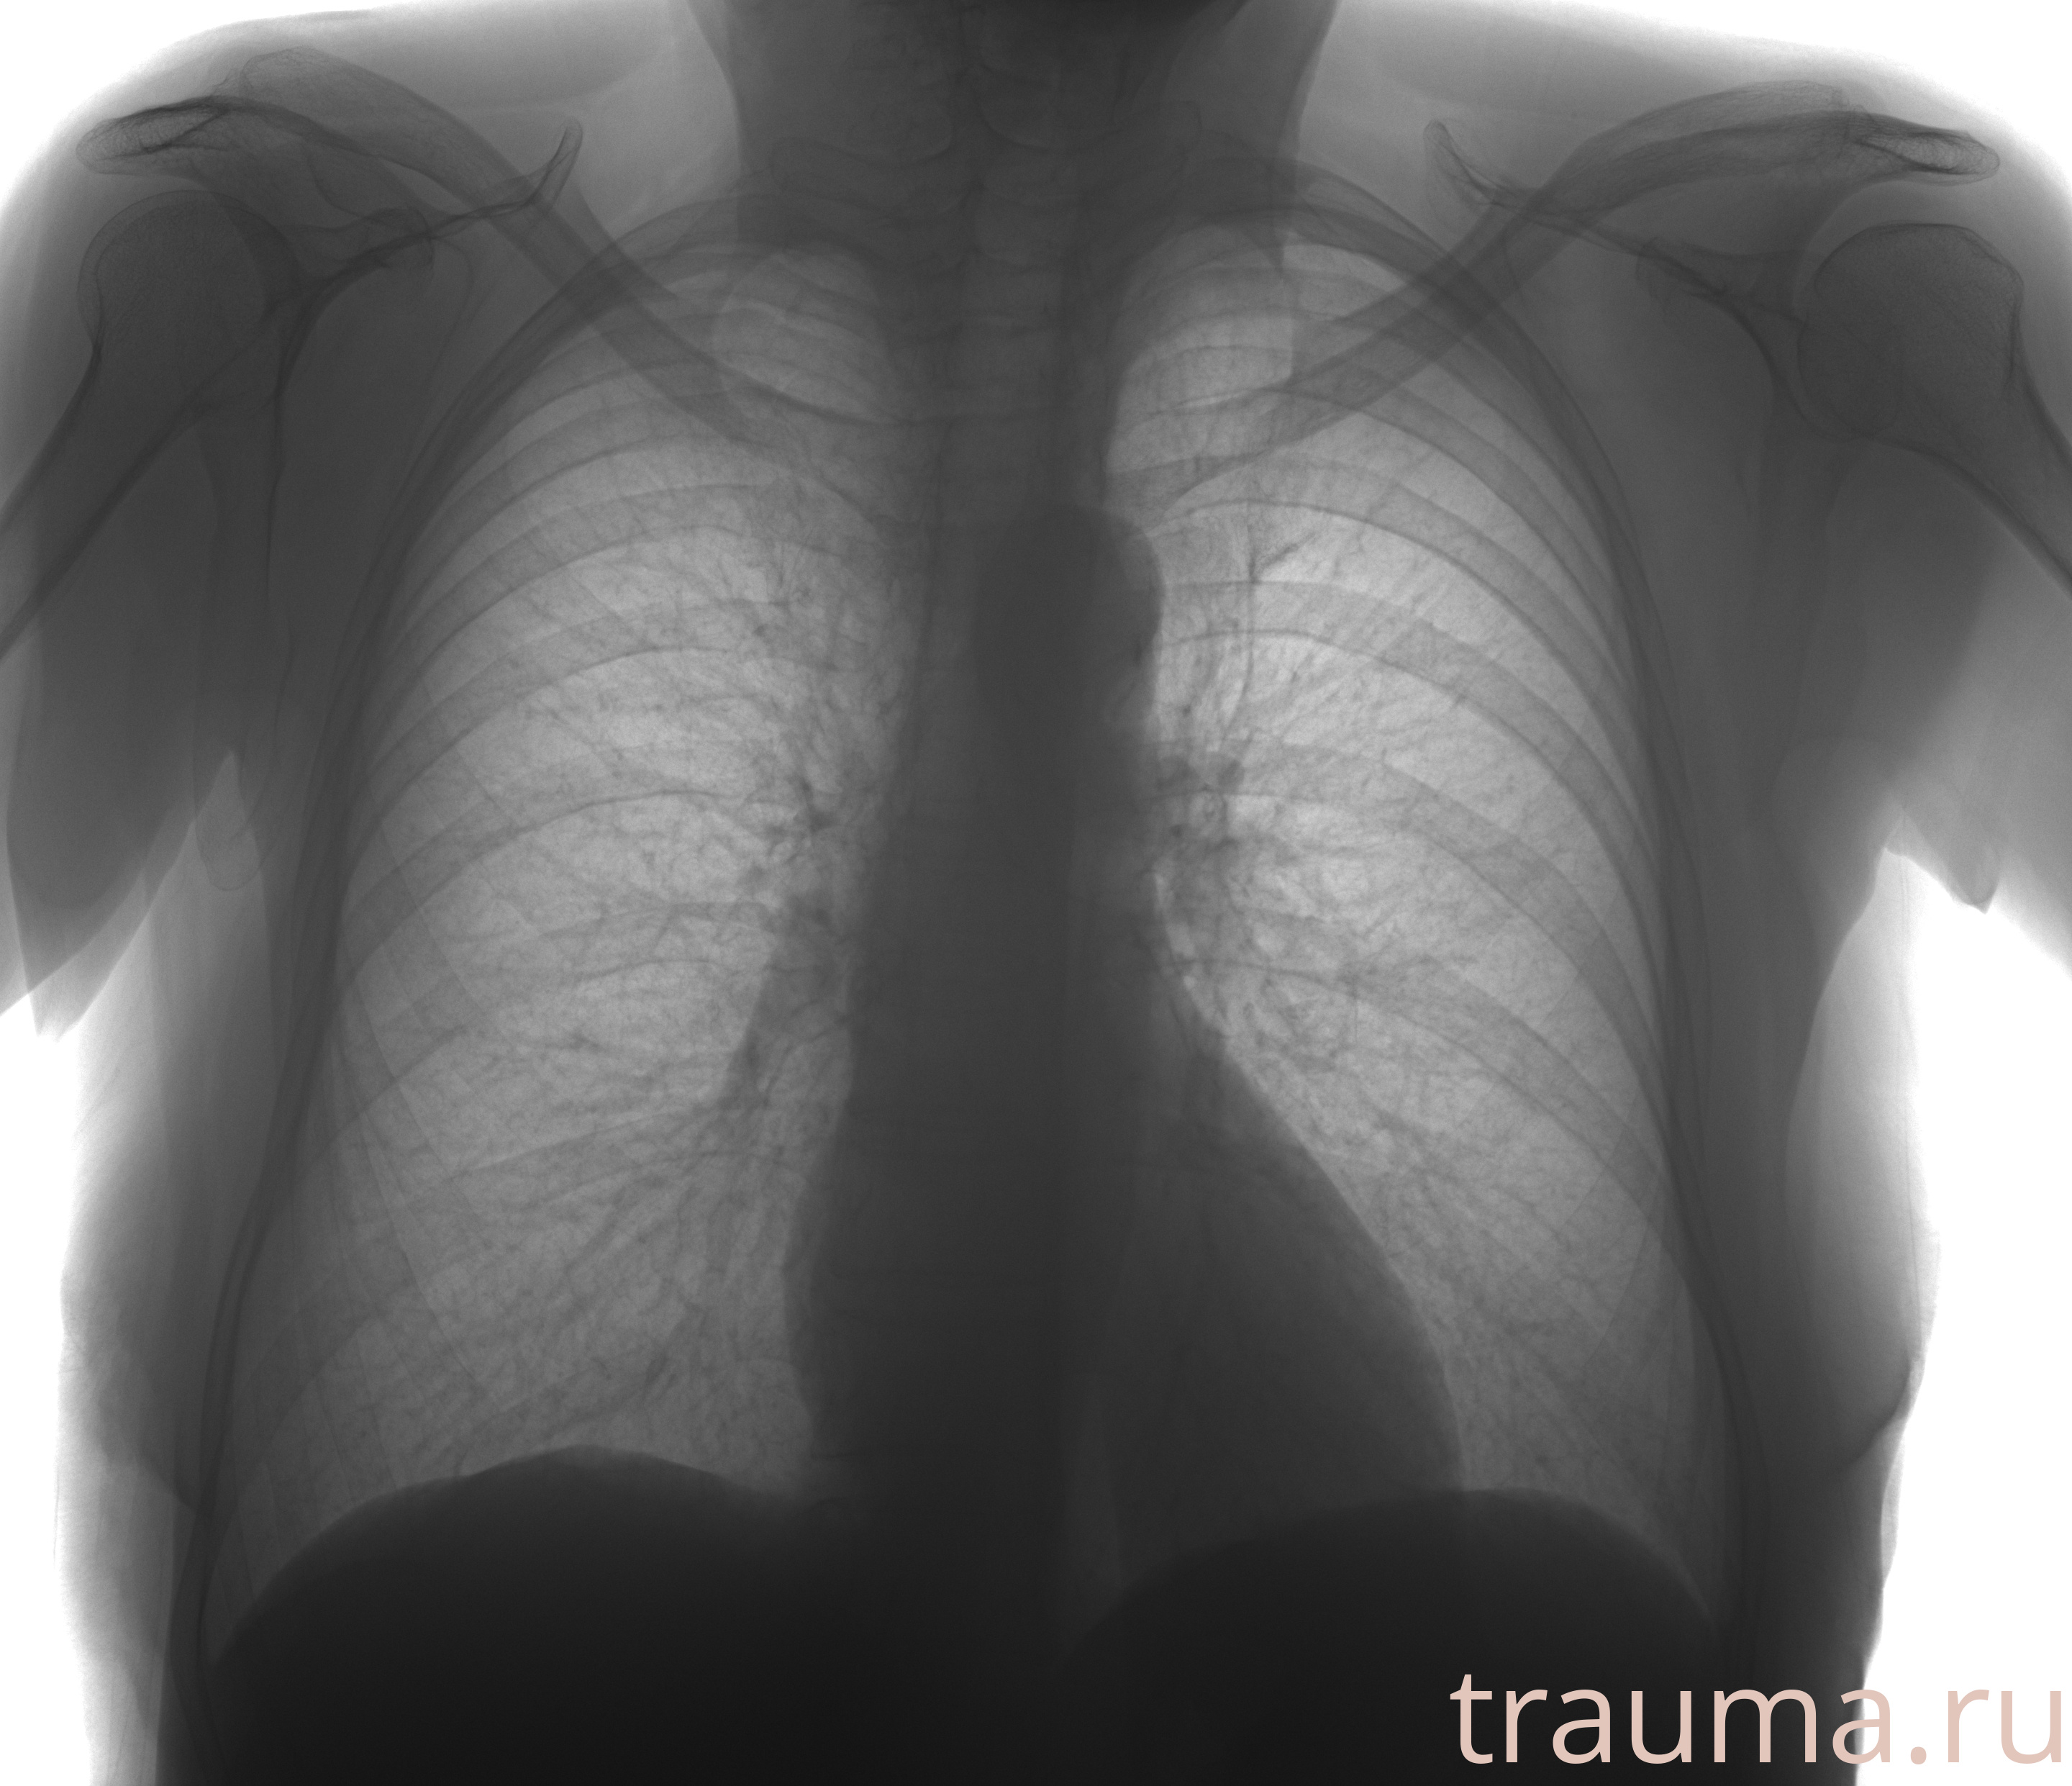

Рентгенограммы

Рентген на дому: по вашему адресу приезжает врач-рентгенолог, травматолог-ортопед с мобильным рентгеновским аппаратом, проводит диагностику травмы или заболевания, делает необходимые рентгенограммы, дает рекомендации по дальнейшему лечению. Получить качественные снимки в домашних условиях возможно благодаря уникальной методике, разработанной МосРентген Центром для института  Склифосовского